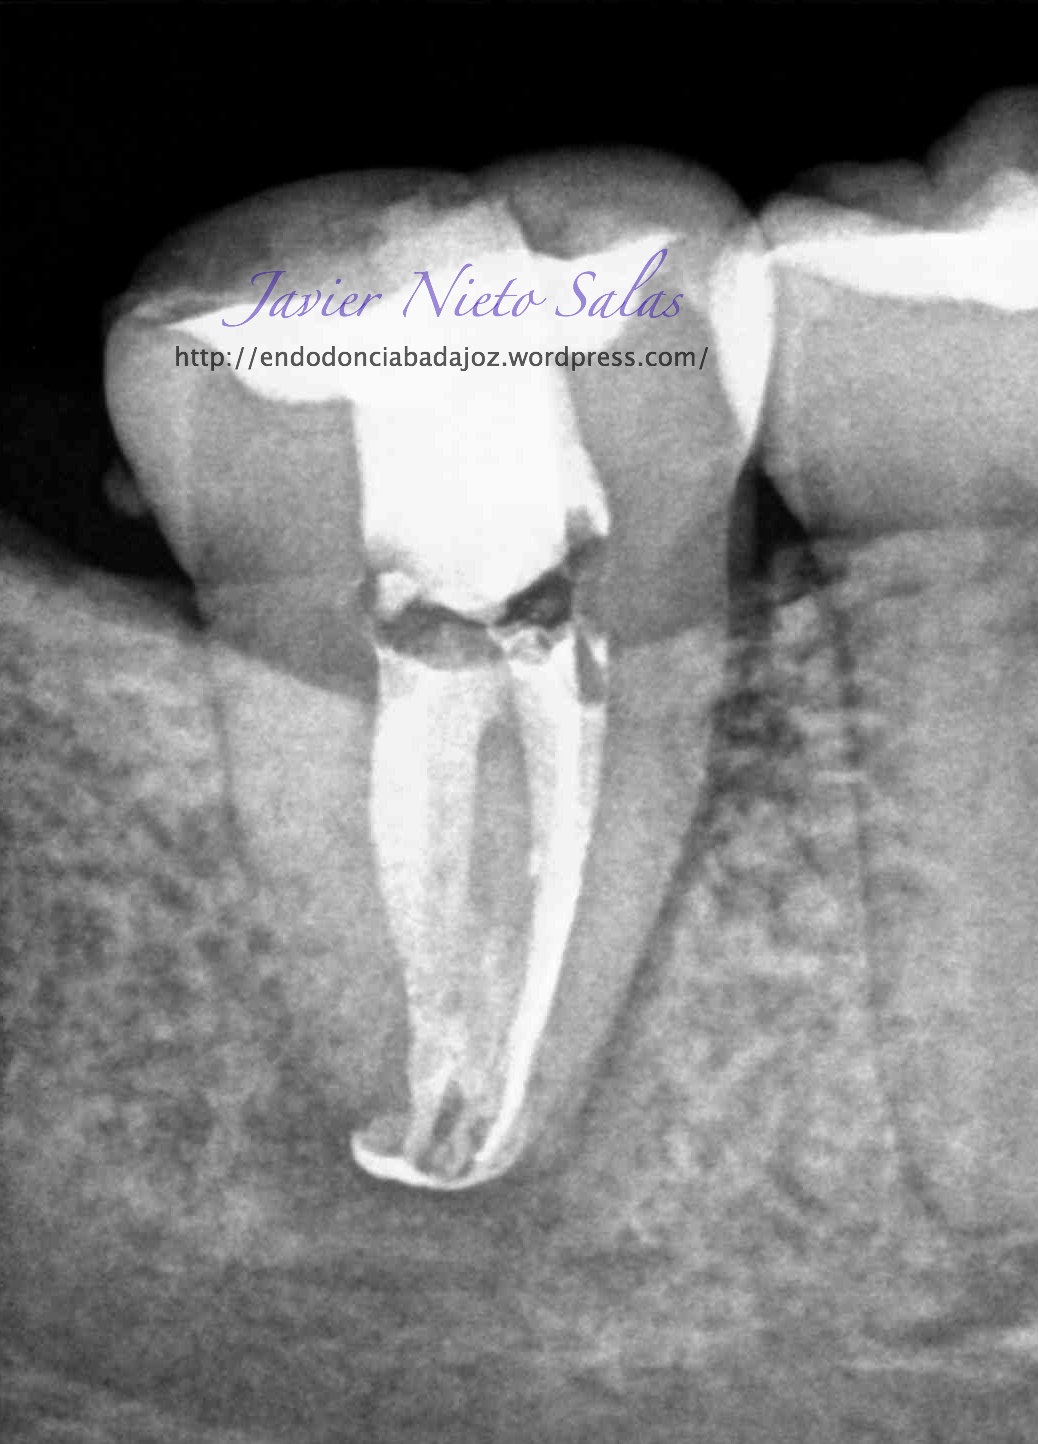

Empezaremos con el primer caso, un 4.7, se trata de una necrosis con afectación periapical.Ante las pruebas diagnósticas, nos fijamos en una fístula muy coronal, un sondaje vestibular puntual, esto nos hace pensar en un diagnóstico diferencial con un Sindrome de Diente fisurado. Sin aparente linea de fisura coronal, no vemos, con la ayuda de la magnificación, linea de fisura, lo que no nos descarta definitivamente que se trate de este síndrome de fisura, pues como ya sabemos pueden aparecer en diferentes tramos de la pieza, clasificando así los diferentes tipos.

Realizamos el tratatamiento de conductos con la sospecha del causante de la necrosis es una fractura vertical, pero no hemos podido ver la linea de fisura.

Se trataría de una cámara pulpar Tipo Ic según la clasificación por el método de Min:

El sistema de Obturación sería con condensación vertical.